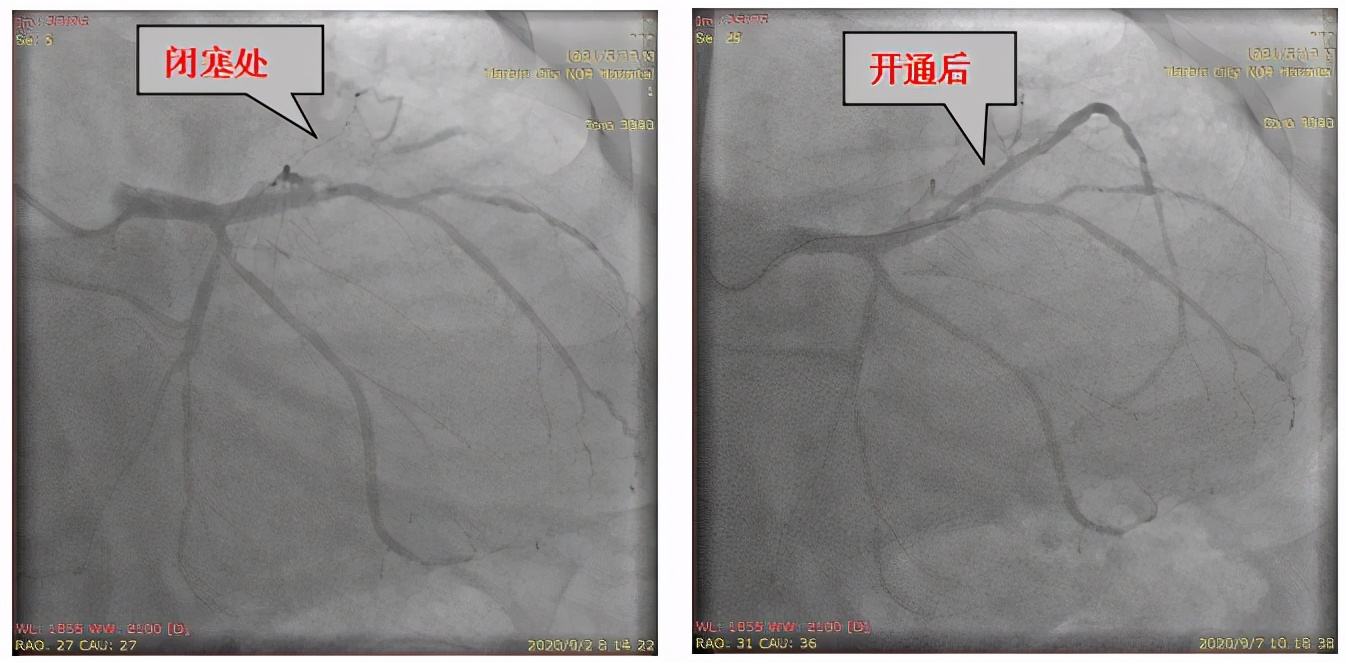

今年8月份的时候,李先生由于逐渐加重的胸闷气短来就诊,经过一系列的检查之后,以 “心力衰竭” 收入院治疗。虽然治疗后病情有所好转,但是心衰的原因还未明确,带着这样的困惑,李先生进行了冠脉造影检查,结果显示 冠状动脉前降支完全堵塞 ,严重影响了心脏供血,这才造成了心力衰竭。

↑ 术前造影 ↑ 术后造影